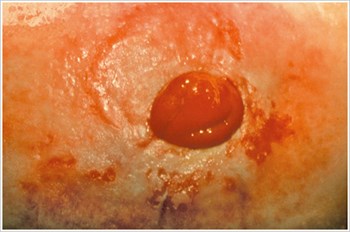

Pyoderma Gangrenosum

Description/Causes:

An inflammatory skin disease often seen in patients with inflammatory bowel disease ( IBD ) such as Crohn's disease or ulcerative colitis.

Symptoms:

- Irregularly shaped, red, painful, infected ulcers, with red-to-purple rolled margins; appear on legs, buttocks, face, and peristomal area.